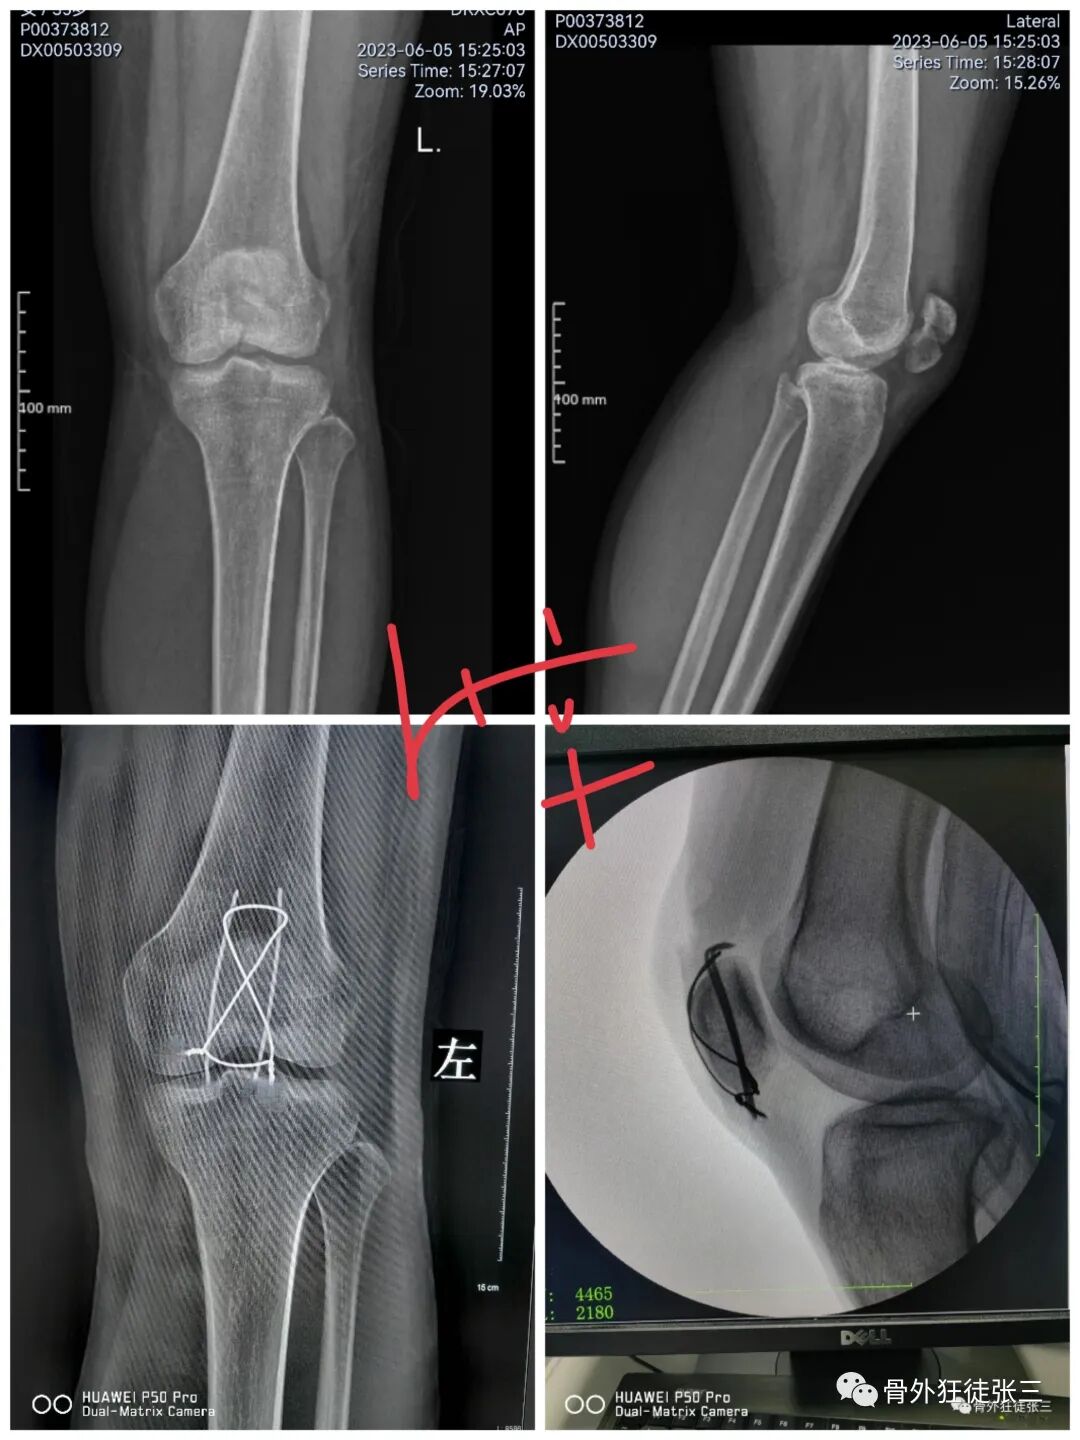

病例14,儿童髁上骨折零切开,桡侧三枚针发散固定

病例15,儿童髁上骨折零切开,

病例16,儿童髁上骨折零切开

病例17,低位髁上骨折零切开

病例18,第一掌骨基底部骨折,闭合复位,克氏针支架

病例24,低位髁上骨折零切开,闭合复位克氏针发散固定

病例25,开放性粉碎性指骨骨折,克氏针固定

病例28,髌骨骨折,克氏针张力带

病例31,儿童髁上骨折零切开,闭合复位克氏针

病例32,第345掌骨开放性骨折,克氏针髓内+克氏针支架

病例35,3型儿童髁上骨折零切开,闭合复位克氏针

病例38,儿童髁上骨折零切开,克氏针发散固定

病例52,高位髁上骨折零切开,闭合穿针

53,儿童髁上骨折零切开,交叉针